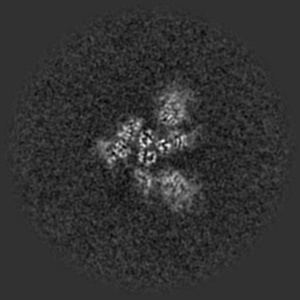

Structure of the SARS-CoV-2 S 2P trimer in complex with the human neutralizing antibody Fab fragment, BG7-20

Sample: Ternary complex of BG7-20 Fab bound to SARS-CoV-2 spike trimer